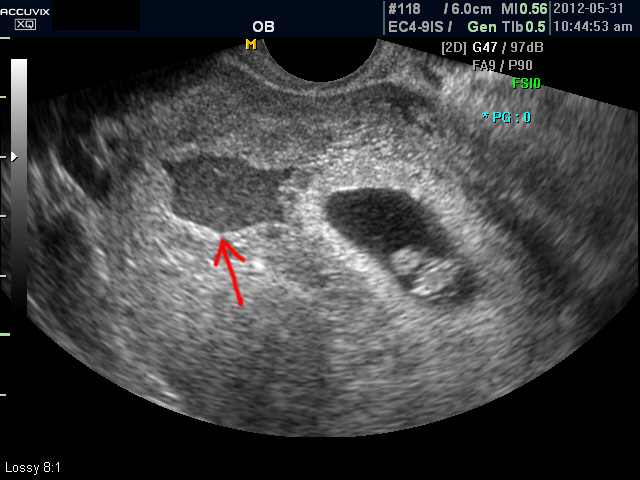

아래는 유산과 관련된 초음파 사진으로 위 사진은 유산기가 있다고 하는 경우 (의학적으로는 절박유산)의 사진이고 아래의 사진은 고사 난자라고 하여 태아가 정상적으로 형성되지 못한 유산의 사례입니다.

초음파 검사에서는 정상 임신으로 진단된 후 아기집 (태낭. G-Sac)이 보이지 않거나 평균 임신 주수에 비하여 아기집이 상당히 작을 때, 그리고 임신 8주 이후에 태아 심박동이 없는 경우에 유산일 가능성이 높다고 판단합니다.